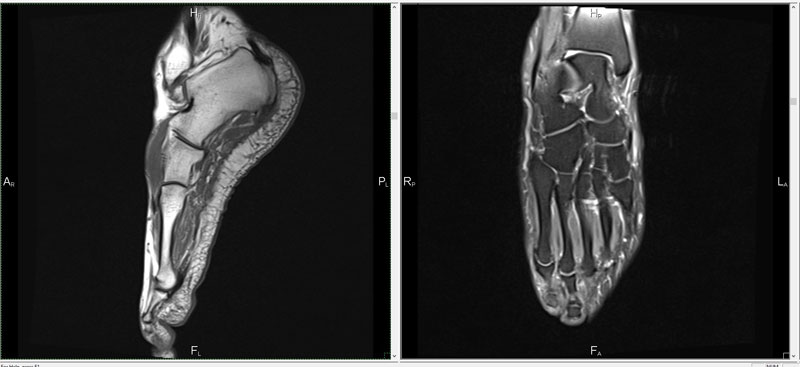

МРТ конечностей в СПб и МоскеМРТ конечностей является самым информативным неинвазивным методом исследования, сканирующим и отражающим точную структуру.

С помощью магнитного поля, радиочастотных импульсов и целой компьютерной системы, врачи получают детальное изображение костей, мягких и хрящевых тканей, волокон сухожилий и прочие мельчайшие структурные элементы конечностей пациента.

Без мрт ноги или руки не обойтись при обследовании суставов, сухожилий, мышц, а также костей пятки, запястья и т.п. Людям, страдающим венозными заболеваниями, рекомендовано делать мрт сосудов ног. Этот метод превосходит УЗИ, потому что врачи подробно изучают как близлежащие, так и глубокие вены и выявляют различные нарушения кровотока. При этом цена мрт сосудов нижних конечностей зависит от типа аппарата, на котором делают процедуру, и применённого контраста.

МРТ костно-мышечной системы конечностей проводят при дегенеративных заболеваниях суставов, метастазах, для оценки состояния сосудов и даже при нарушениях кровообращения. С его помощью обнаруживают наличие воспалительных и опухолевых процессов в костях и мягких тканях.

При болях в запястье, подозрении на остеомиелит показано мр исследование кисти, с его помощью диагностируют абсцессы, ганглиозные кисты, повреждения нервов, мышц и прочие болезни. МРТ лодыжки назначают чаще для диагностики травм связок, сухожилий, а также костей.